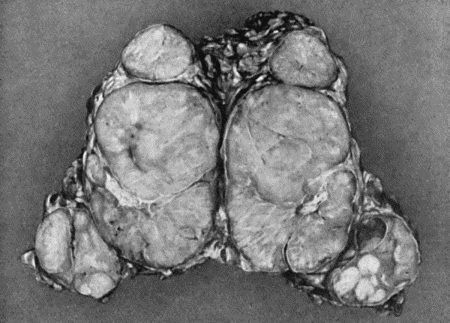

19554.

Fibro-myoma of Uterus

196 55.Recurrent Sarcoma of Sciatic Nerve

198 56.Sarcoma of Arm fungating

199 57.Carcinoma of Breast